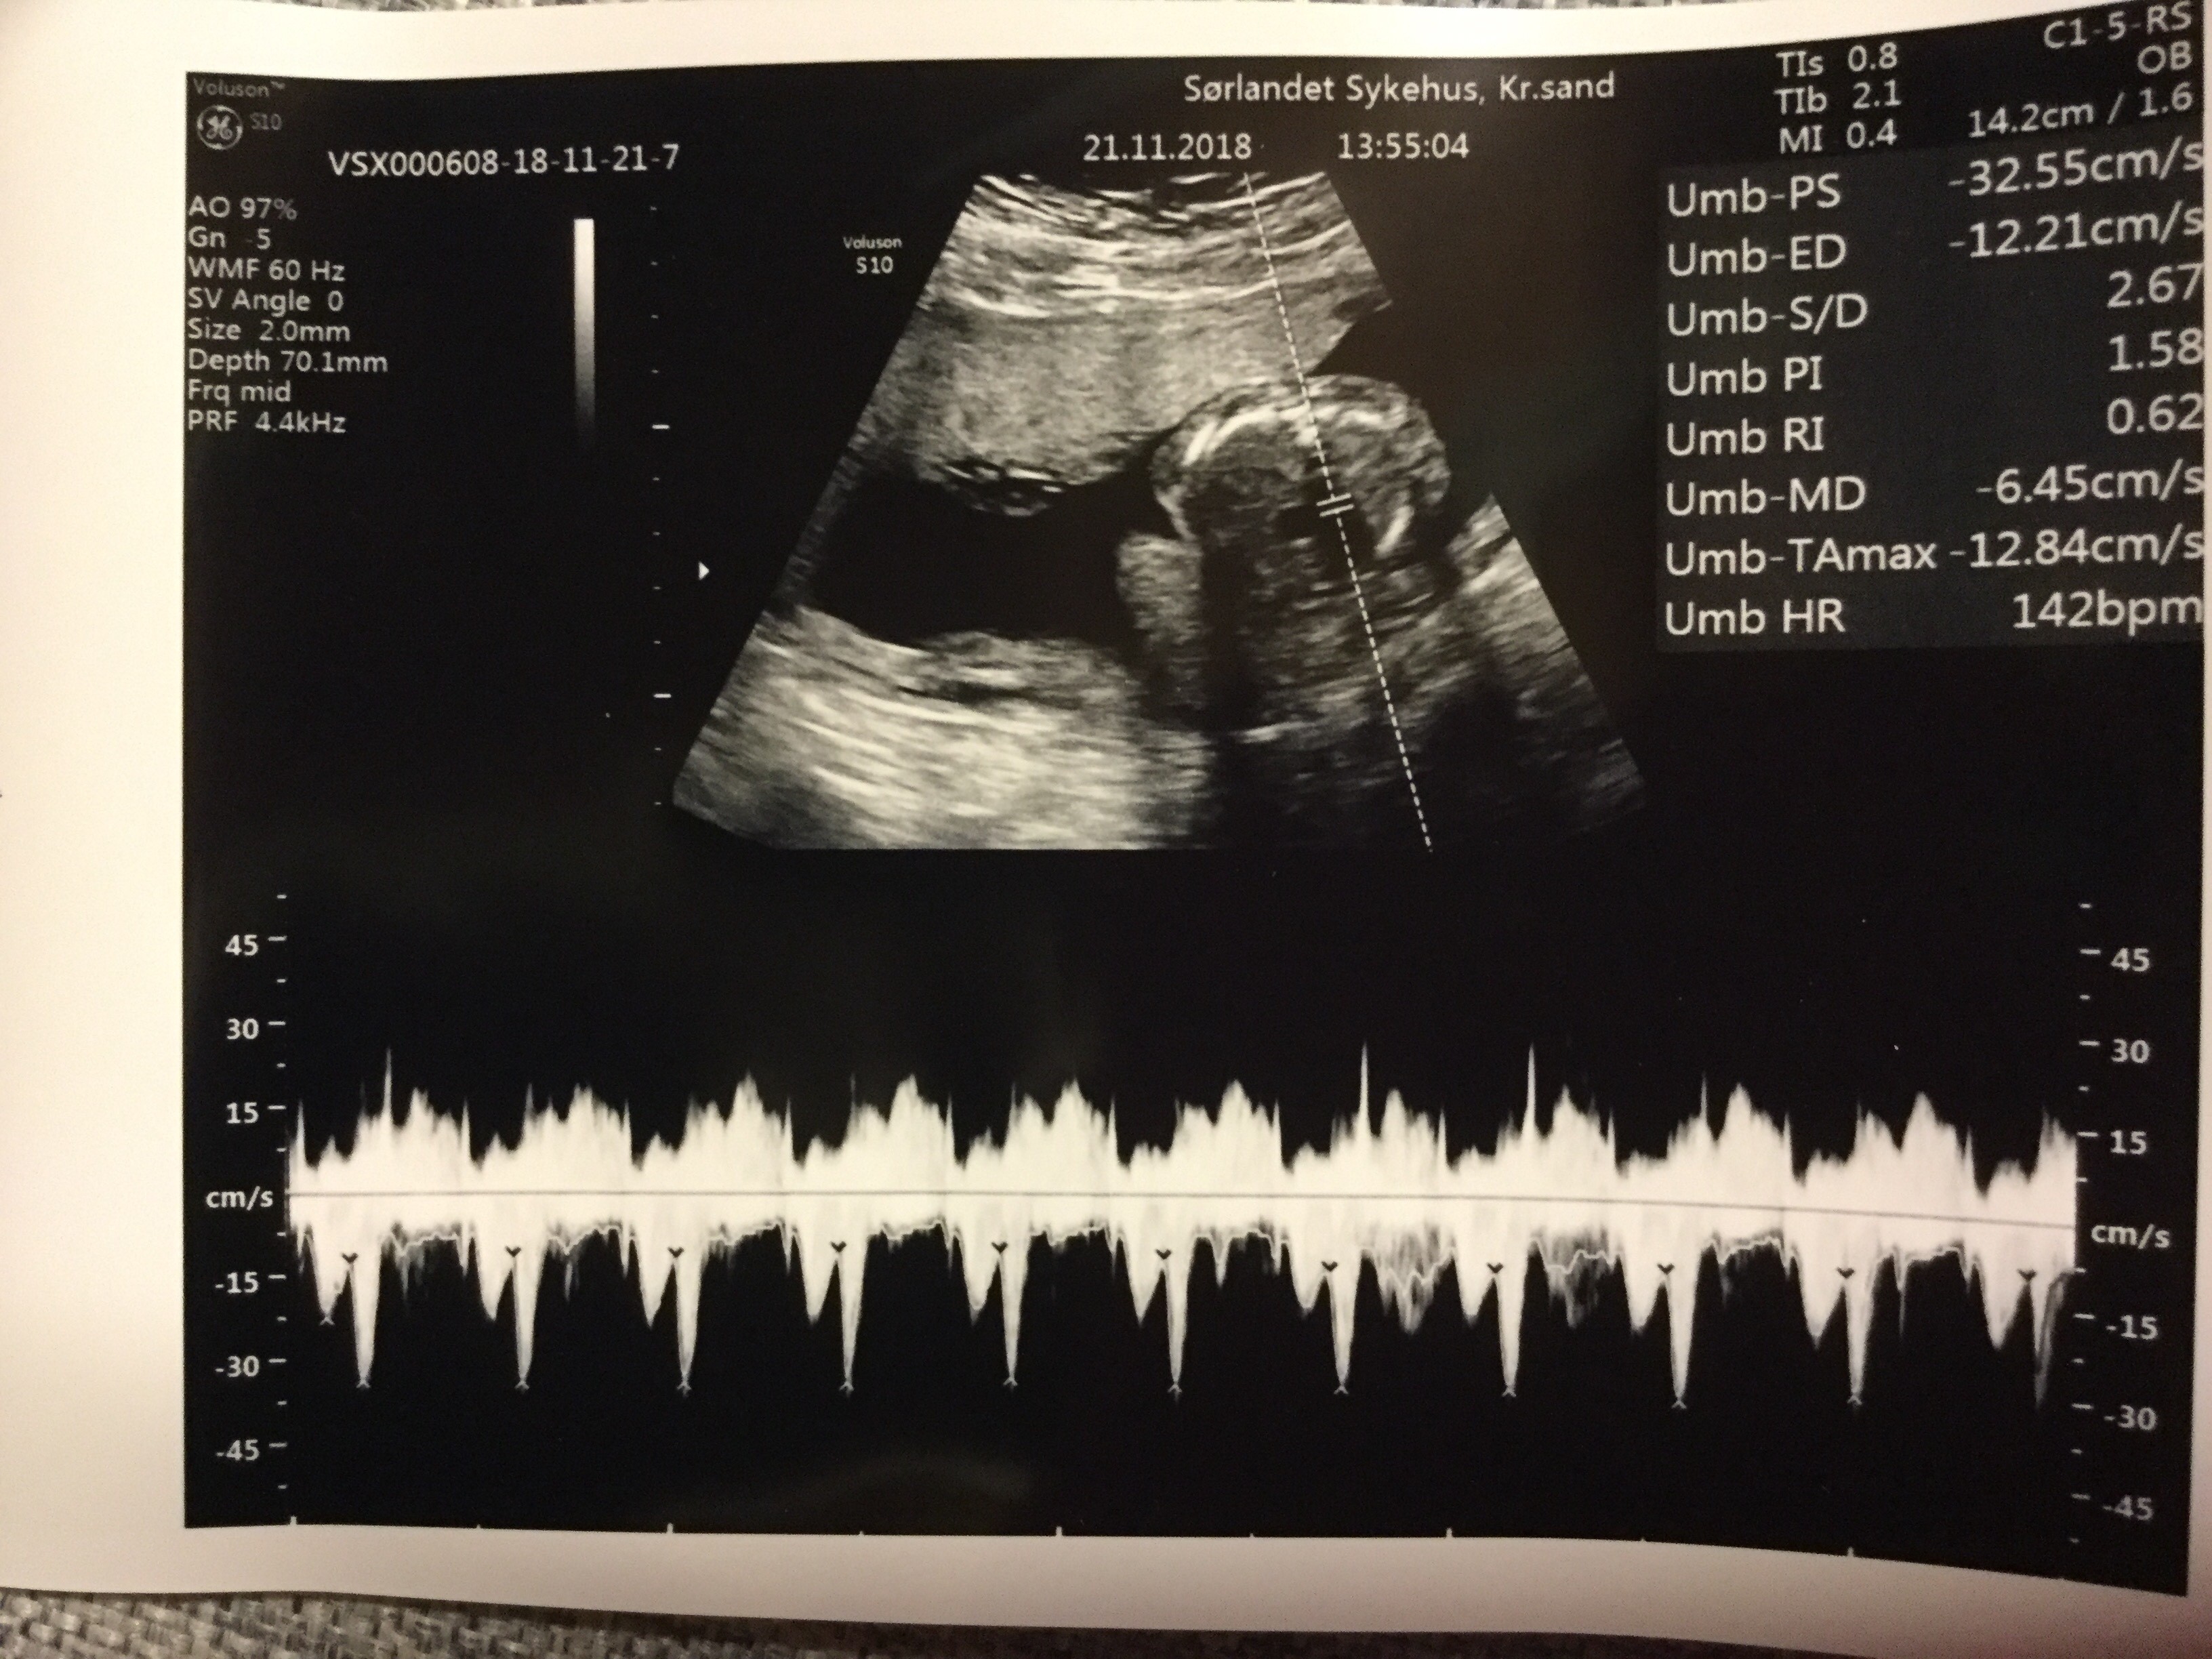

19+0 (wg usg i tego się teraz trzymamy!) wg OM 20+0

Waga : prawie 250 g i prawie 22 cm :biggrin2:

Tętno : 144(wczoraj), 150 (dzisiaj) :biggrin2:

Płeć : 100% chłopak :-) :)

Imię : Gabriel Mirosław :biggrin2:

Nosek - widoczny i śliczniutki (na prenatalnych podobno kośc nosowa była „nie do oceny”!)

Łożysko : na przedniej ścianie

Szyjka : 5 cm

Wszystkie narządy rozwijają się prawidłowo :-) :)

Termin porodu wg usg 20.04.2019 (jednak ze względu na cukrzycę typu2 nastąpi on 2 tygodnie wcześniej,ale konkretną datę poznam w późniejszym terminie) :-) :)